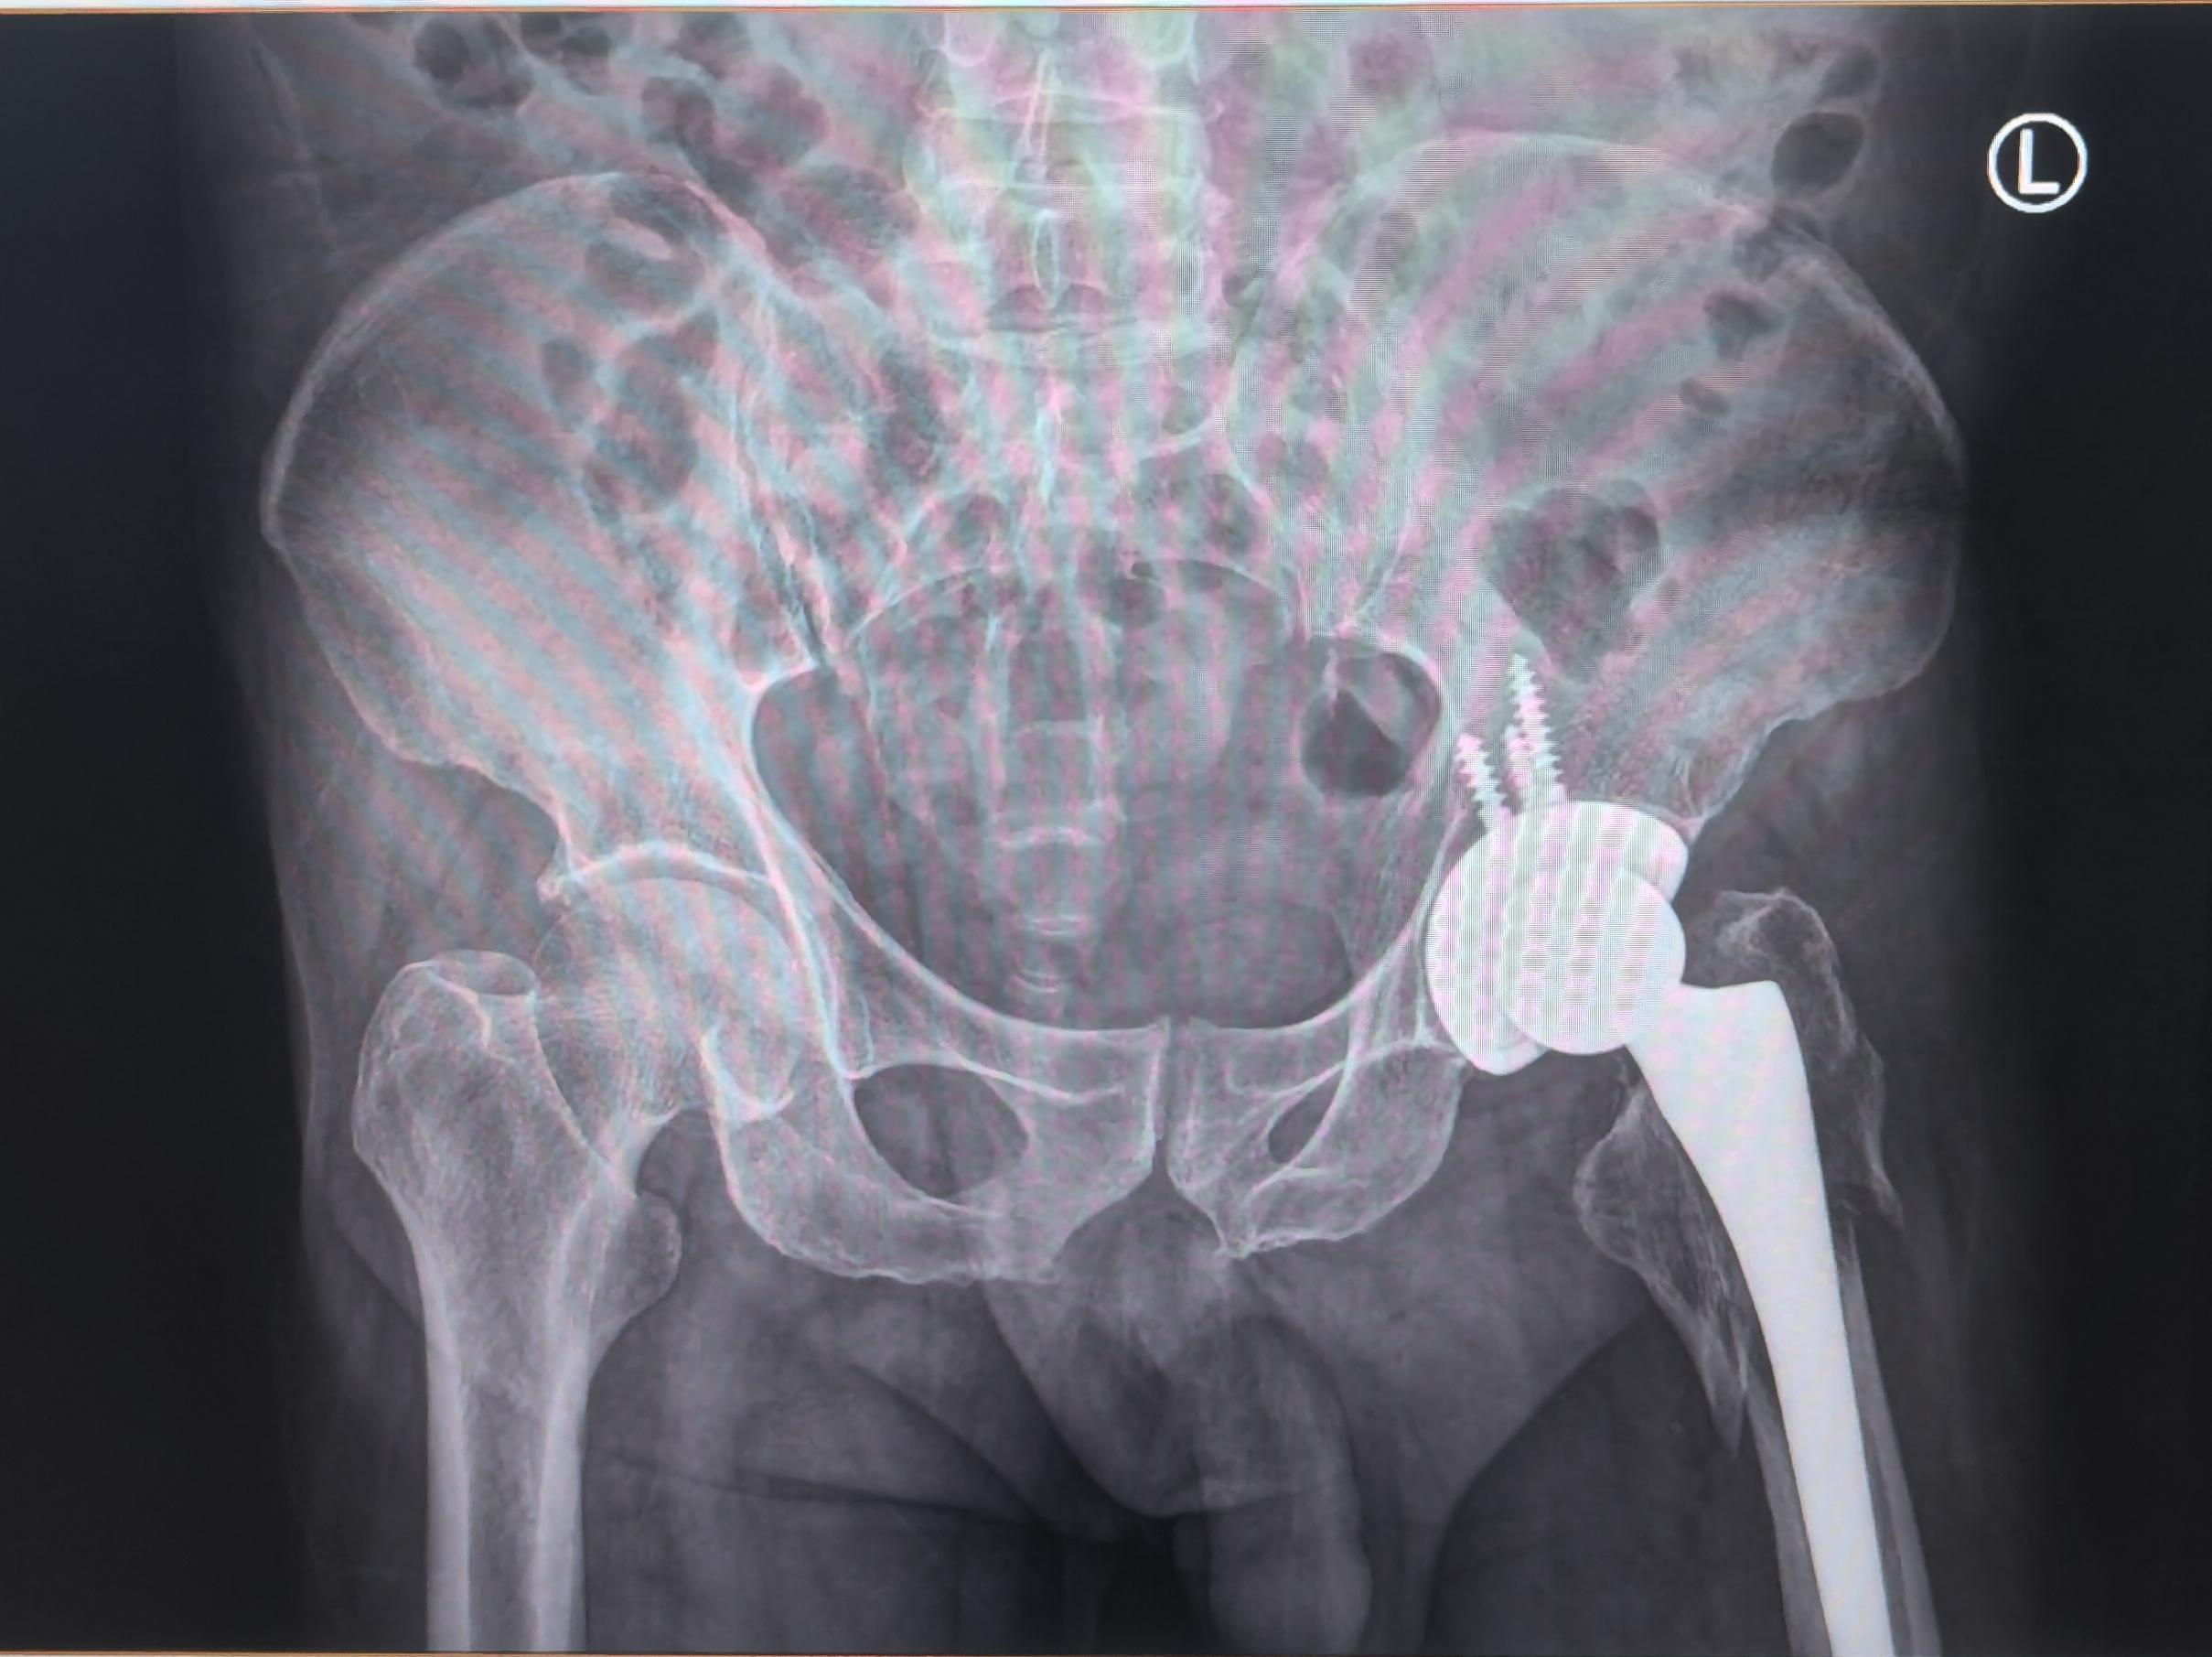

髋关节置换术后假体周围骨折。老年人一定要重视骨质疏松的预防(抗骨质疏松、适当运动、防跌倒),避免出现假体周围骨折的情况,虽然可以手术治疗,两天后也可以下床,但是创伤要比第一次大。